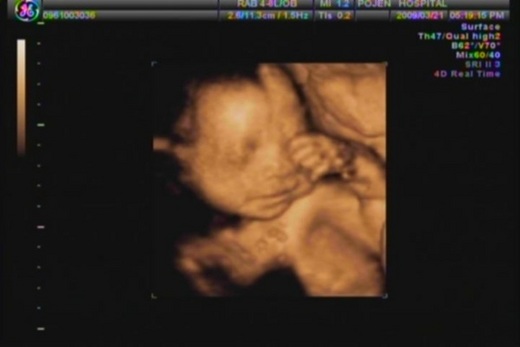

PS:照片是我們NEMO廿六週大時去照的4D,不曉得夢到了什麼還在偷笑呢!可愛吧!